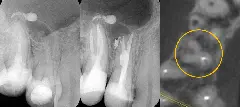

Тратите 40 минут на поиск устья облитерированного канала? Боитесь перфорации дна полости? Аксиальный срез КЛКТ — ваш GPS-навигатор в эндодонтии. Узнайте, как находить устья за 3 минуты, снизить риск осложнений и работать уверенно. Пошаговая методика с клиническим кейсом от практикующего эндодонтиста.